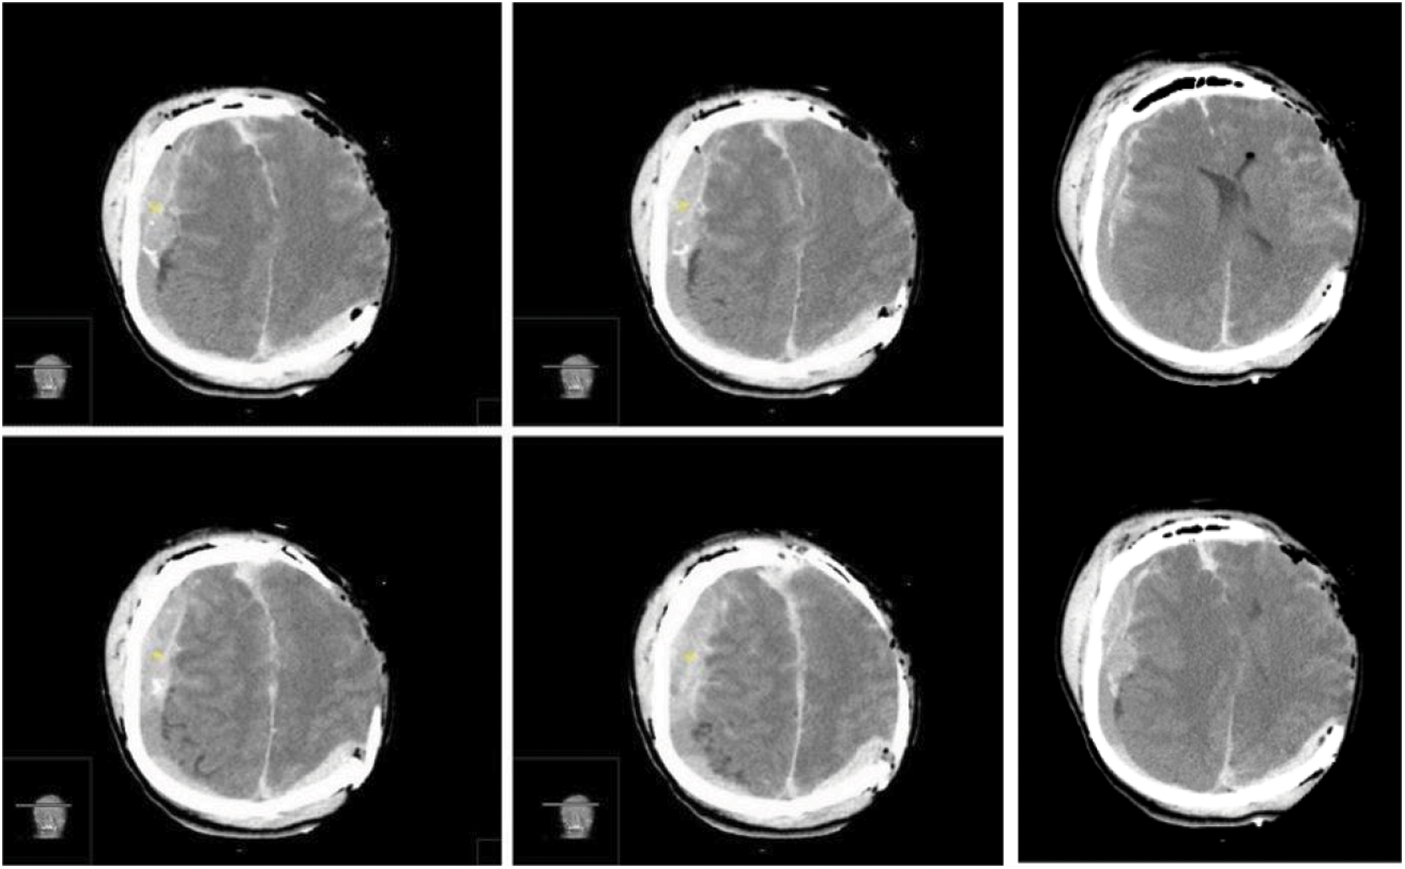

A left decompressive craniectomy was performed, and a substantial epidural blood collection was removed. Once the dura mater was opened, a concomitant massive acute SDH was detected and removed. During surgery, the brain showed progressive swelling, which made replacing the bone flap impossible. We performed a duroplasty and skin closure, as usual, along with a subgaleal drain. Due to the patient’s right anisocoria, an urgent postoperative CT scan was needed, which revealed a massive blood collection in the right hemisphere, with left midline shift (Fig. 4).

Figure 4: Immediate post-operative brain CT scan images in series revealing a massive concomitant right hemispheric acute extra-subdural hematoma, with left midline shift. In this case the “CT comma sign” and the detached dura are visible in the axial sequences (Yellow asterisks)

We completed the procedure with satisfying hemostasis, duroplasty, and repositioning of the bone flap; also in this case, a subgaleal drain was placed. After surgery, the patient was isochoric again, and a further postoperative CT scan revealed common postoperative findings and a proper brain decompression (Fig. 6).

Figure 6: Postoperative CT scan images in series showing common postoperative findings and a bilateral proper brain decompression